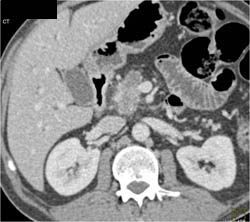

Lymphangioma